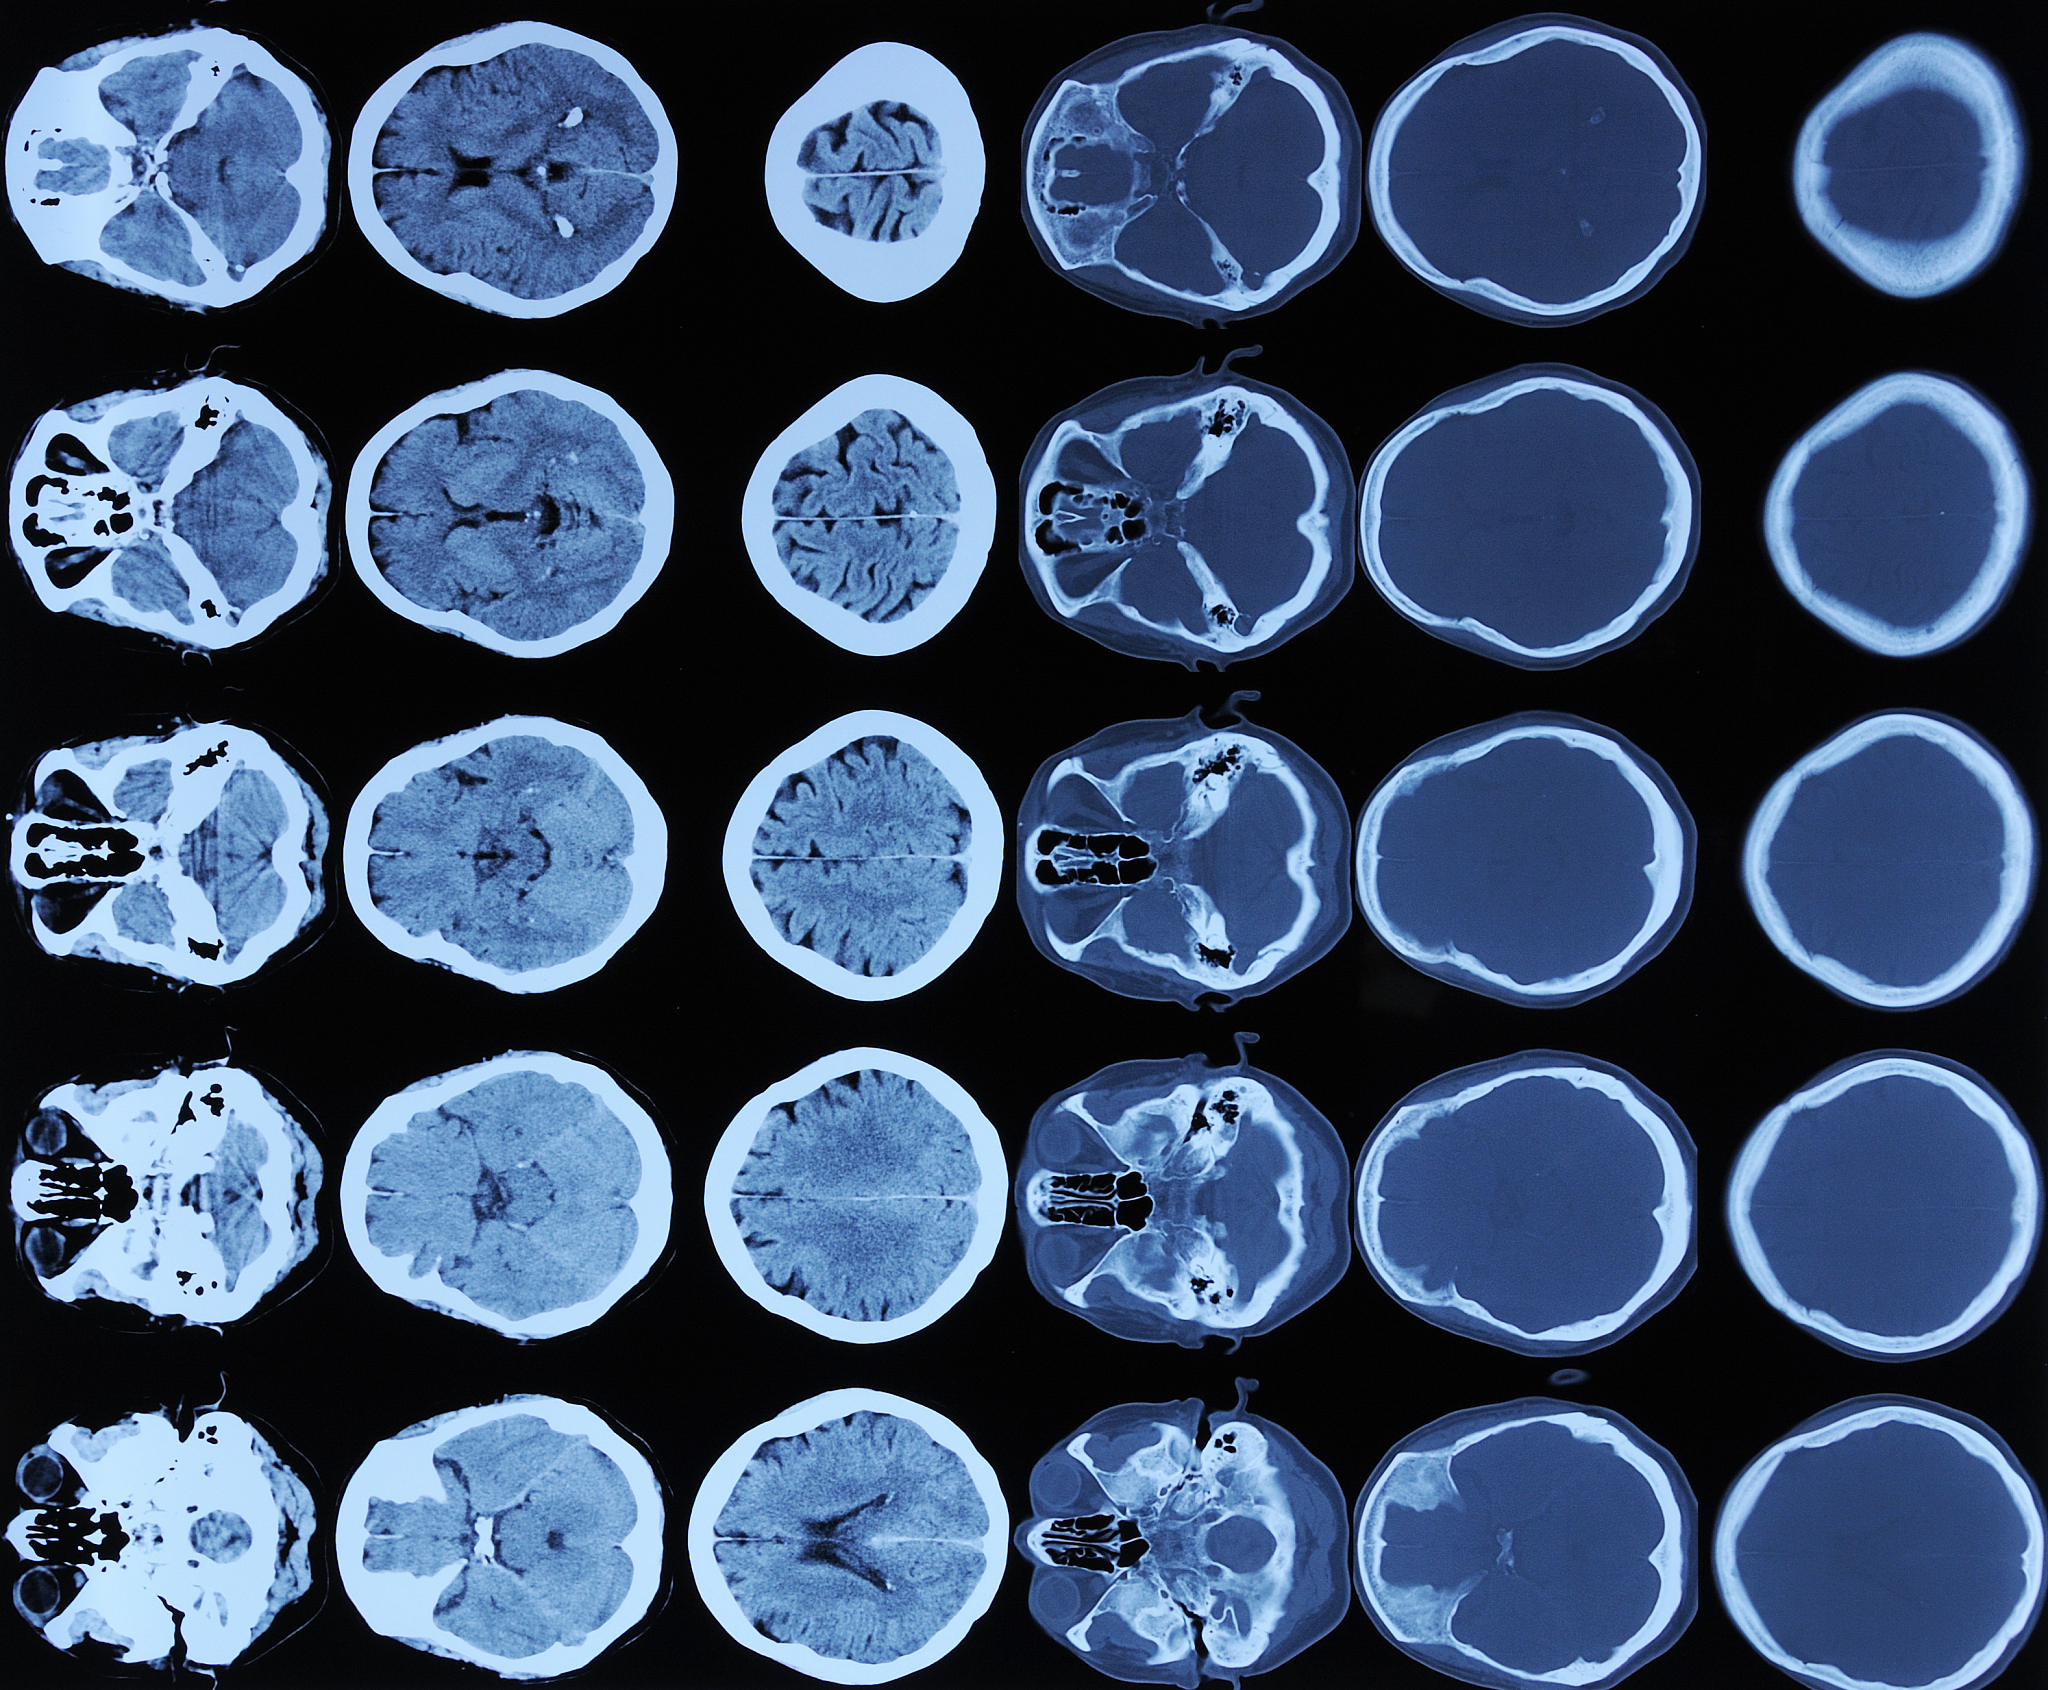

International MICCAI Brainlesion Workshop是一个国际性的学术研讨会,主要关注脑病变的图像分析和计算机辅助诊断。它是MICCAI(Medical Image Computing and Computer Assisted Intervention)会议的附属研讨会之一,每年举办一次。